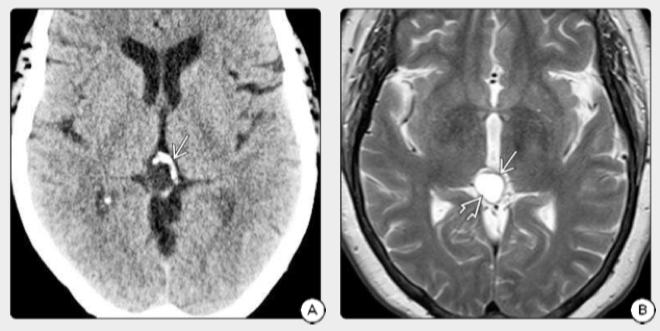

图2:A.CT扫描显示了典型的边缘高密度表现,出现在囊性松果体上的钙质向病灶的“爆炸”型边缘。B.同一患者的T2WI显示囊肿被薄薄的实体组织边缘包围。C.FLAIR扫描显示,囊壁轻度强化,囊液没有被控制。D.T1 C+FS证实囊肿壁增。术后病理证实该例为松果体细胞瘤。